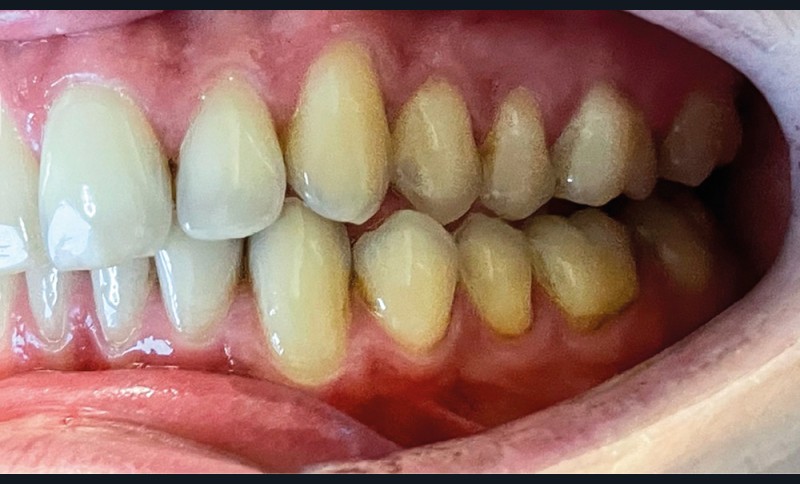

► L’entretien semi-directif met en évidence des signes d’apparition récente (un an environ), une aggravation progressive des symptômes, et la perception rapportée par le patient de moindres contacts occlusaux du côté gauche. L’examen clinique extra-oral révèle des douleurs musculaires lors de la palpation des muscles masséters, temporaux et ptérygoïdien médial gauche ainsi que des muscles sterno-cléïdo-occipito-mastoïdiens droit et gauche. Il n’y a pas de limitations d’ouverture buccale. L’examen clinique intra-oral révèle la présence d’une inocclusion dentaire gauche, qui s’étend des dents 23 à 27 (fig. 1 et 2). Il est à noter que la reprise de l’entretien ne rapporte pas d’antécédent de soins dentaires, orthodontiques et/ou prothétiques susceptibles d’engendrer une modification de l’occlusion.